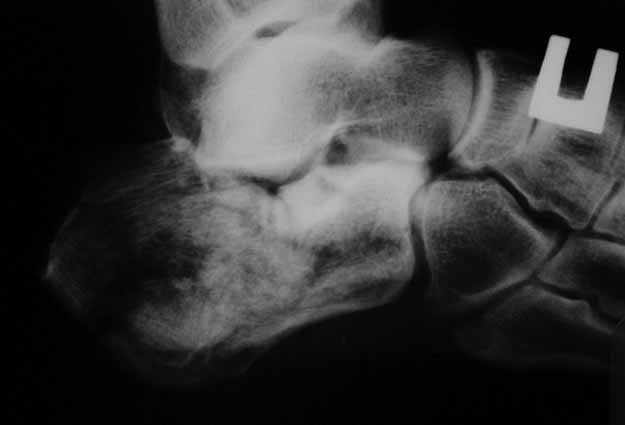

КТ перелома пяточной кости Пациент 60 лет с производственной травмой-закрытые переломы правой пяточной кости, тибиального плато слева поступил в феврале с.г. На 4 сутки выполнена открытая репозиция, остеосинтез внутрисуставного перелома голени, ручная репозиция пяточной кости. Через три месяца начал ходить с нагрузкой на обе ноги. Консолидация голени с полным восстановлением функции колена. Правая стопа умеренно отечна, продольно распластана, длительная ходьба вызывает боли и увеличение отека. Прошел несколько курсов ударно-волновой терапии, грязелечение, боли и отек уменьшились. В наших планах -оформление на ВТЭК, через год возможно выполнение подтаранного артродеза.Но после производства КТ в августе появились сомнения в консолидации перелома.Ранее у нас не было опыта КТ переломов стопы и сканы привели в замешательство.Прилагаю снимки со дня поступления, августовские пациентом не представлены.С благодарностью примем советы коллег.

Данное исследование сделано в неправильной позиции стопы, стопа находится под прямым углом. Но несмотря на это, здесь можно увидеть, что латеральная стенка смещена, фиброз между фрагментами и варусное смещение пятки.

А по поводу тактики лечения, что можно добиться ожиданием в течение года? Дополнительное страдание? Реология, магниты с ударно-волновой терапией без кардинальной операции не исправят варус, а также проявления псевдоотеков с наружной стороны.

Нет срочности, но необходимо исправить варус и сделать субталарный артродез. Латеральное положение, расширенный доступ и closed wedge остеотомия с открытым кнаружи углом, возможно, удастся визуализировать через линию остеотомии недостающие части медиальной стенки - костный графт. Дистракция и после подготовки поверхности кости субталарный дистракционный артродез с помощью костного блока, взятого из крыла. Достаточно двух 6.5мм канюлированных шурупов из пяточного бугра медиально и латерально в направлении таранной кости. Из-за увеличения высоты стопы после артродеза кожа закрывается трудно, и могут быть краевые некрозы, которые лечатся долгими перевязками. Нужна предоперационная беседа по поводу задержки заживления, тогда больные встречают проблемы с пониманием.